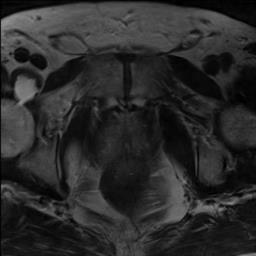

Modern deep neural networks struggle to transfer knowledge and generalize across diverse domains when deployed to real-world applications. Currently, domain generalization (DG) is introduced to learn a universal representation from multiple domains to improve the network generalization ability on unseen domains. However, previous DG methods only focus on the data-level consistency scheme without considering the synergistic regularization among different consistency schemes. In this paper, we present a novel Hierarchical Consistency framework for Domain Generalization (HCDG) by integrating Extrinsic Consistency and Intrinsic Consistency synergistically. Particularly, for the Extrinsic Consistency, we leverage the knowledge across multiple source domains to enforce data-level consistency. To better enhance such consistency, we design a novel Amplitude Gaussian-mixing strategy into Fourier-based data augmentation called DomainUp. For the Intrinsic Consistency, we perform task-level consistency for the same instance under the dual-task scenario. We evaluate the proposed HCDG framework on two medical image segmentation tasks, i.e., optic cup/disc segmentation on fundus images and prostate MRI segmentation. Extensive experimental results manifest the effectiveness and versatility of our HCDG framework.